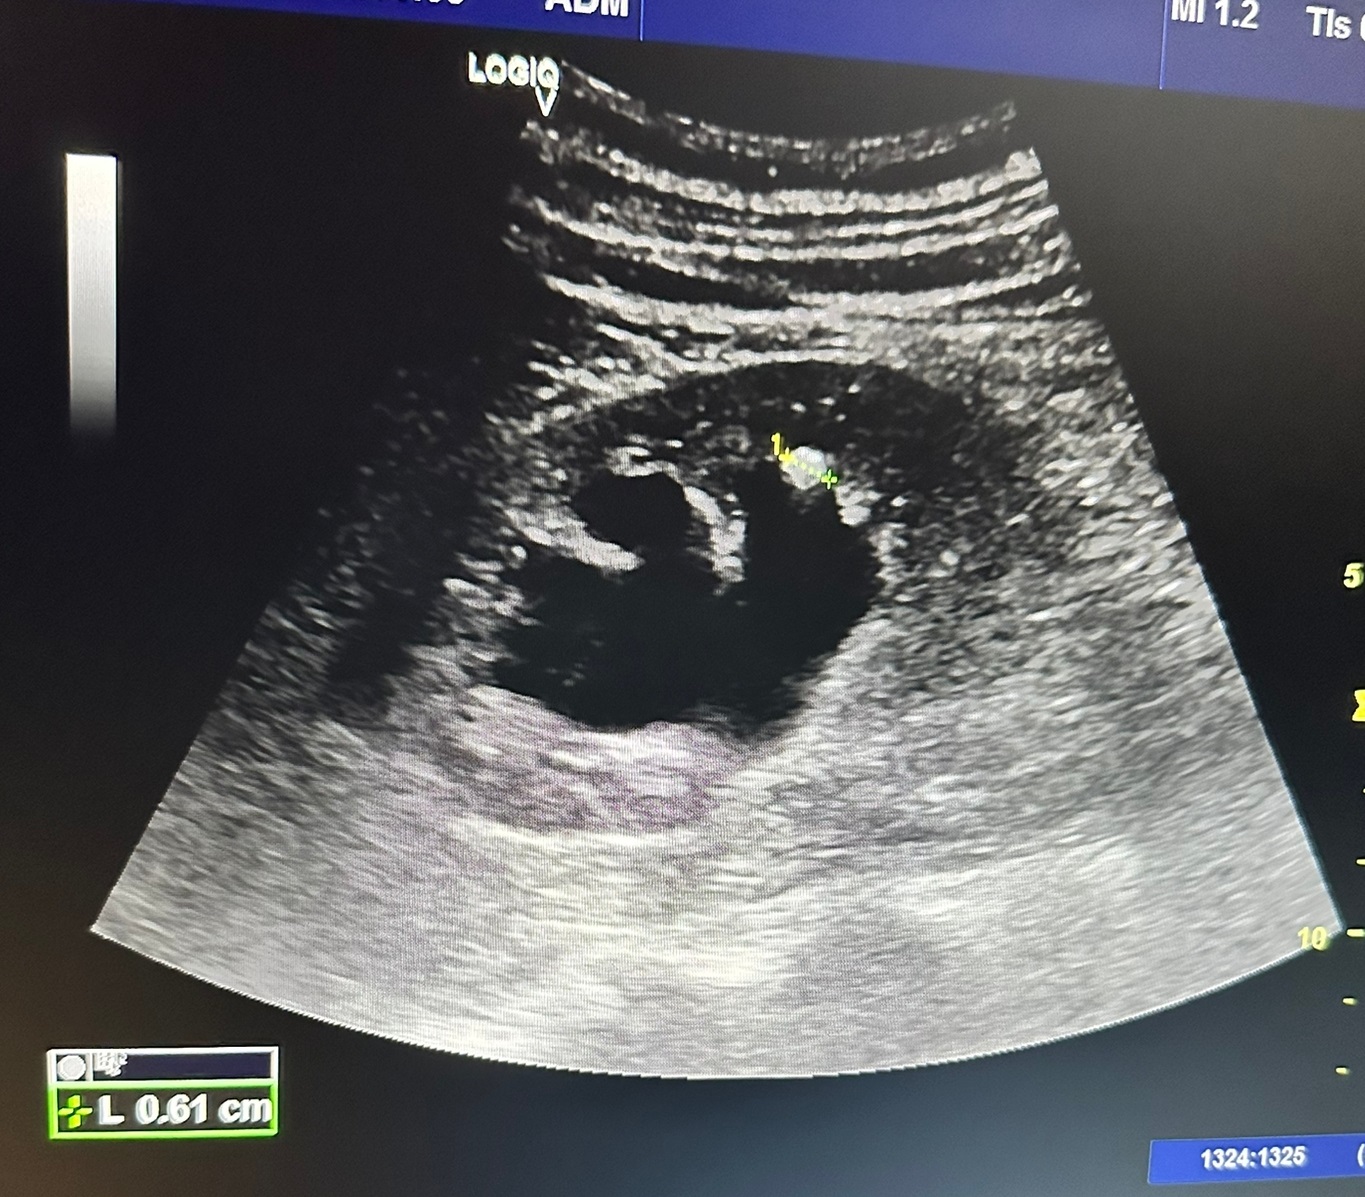

Hallazgos ecográficos

En la valoración se observa riñón derecho con marcada hidronefrosis grado 3, observándose pelvis renal grande, calices dilatados y parenquima normal. Presenta una litiasis de 0,73 cm en el polo inferior del riñon derecho.